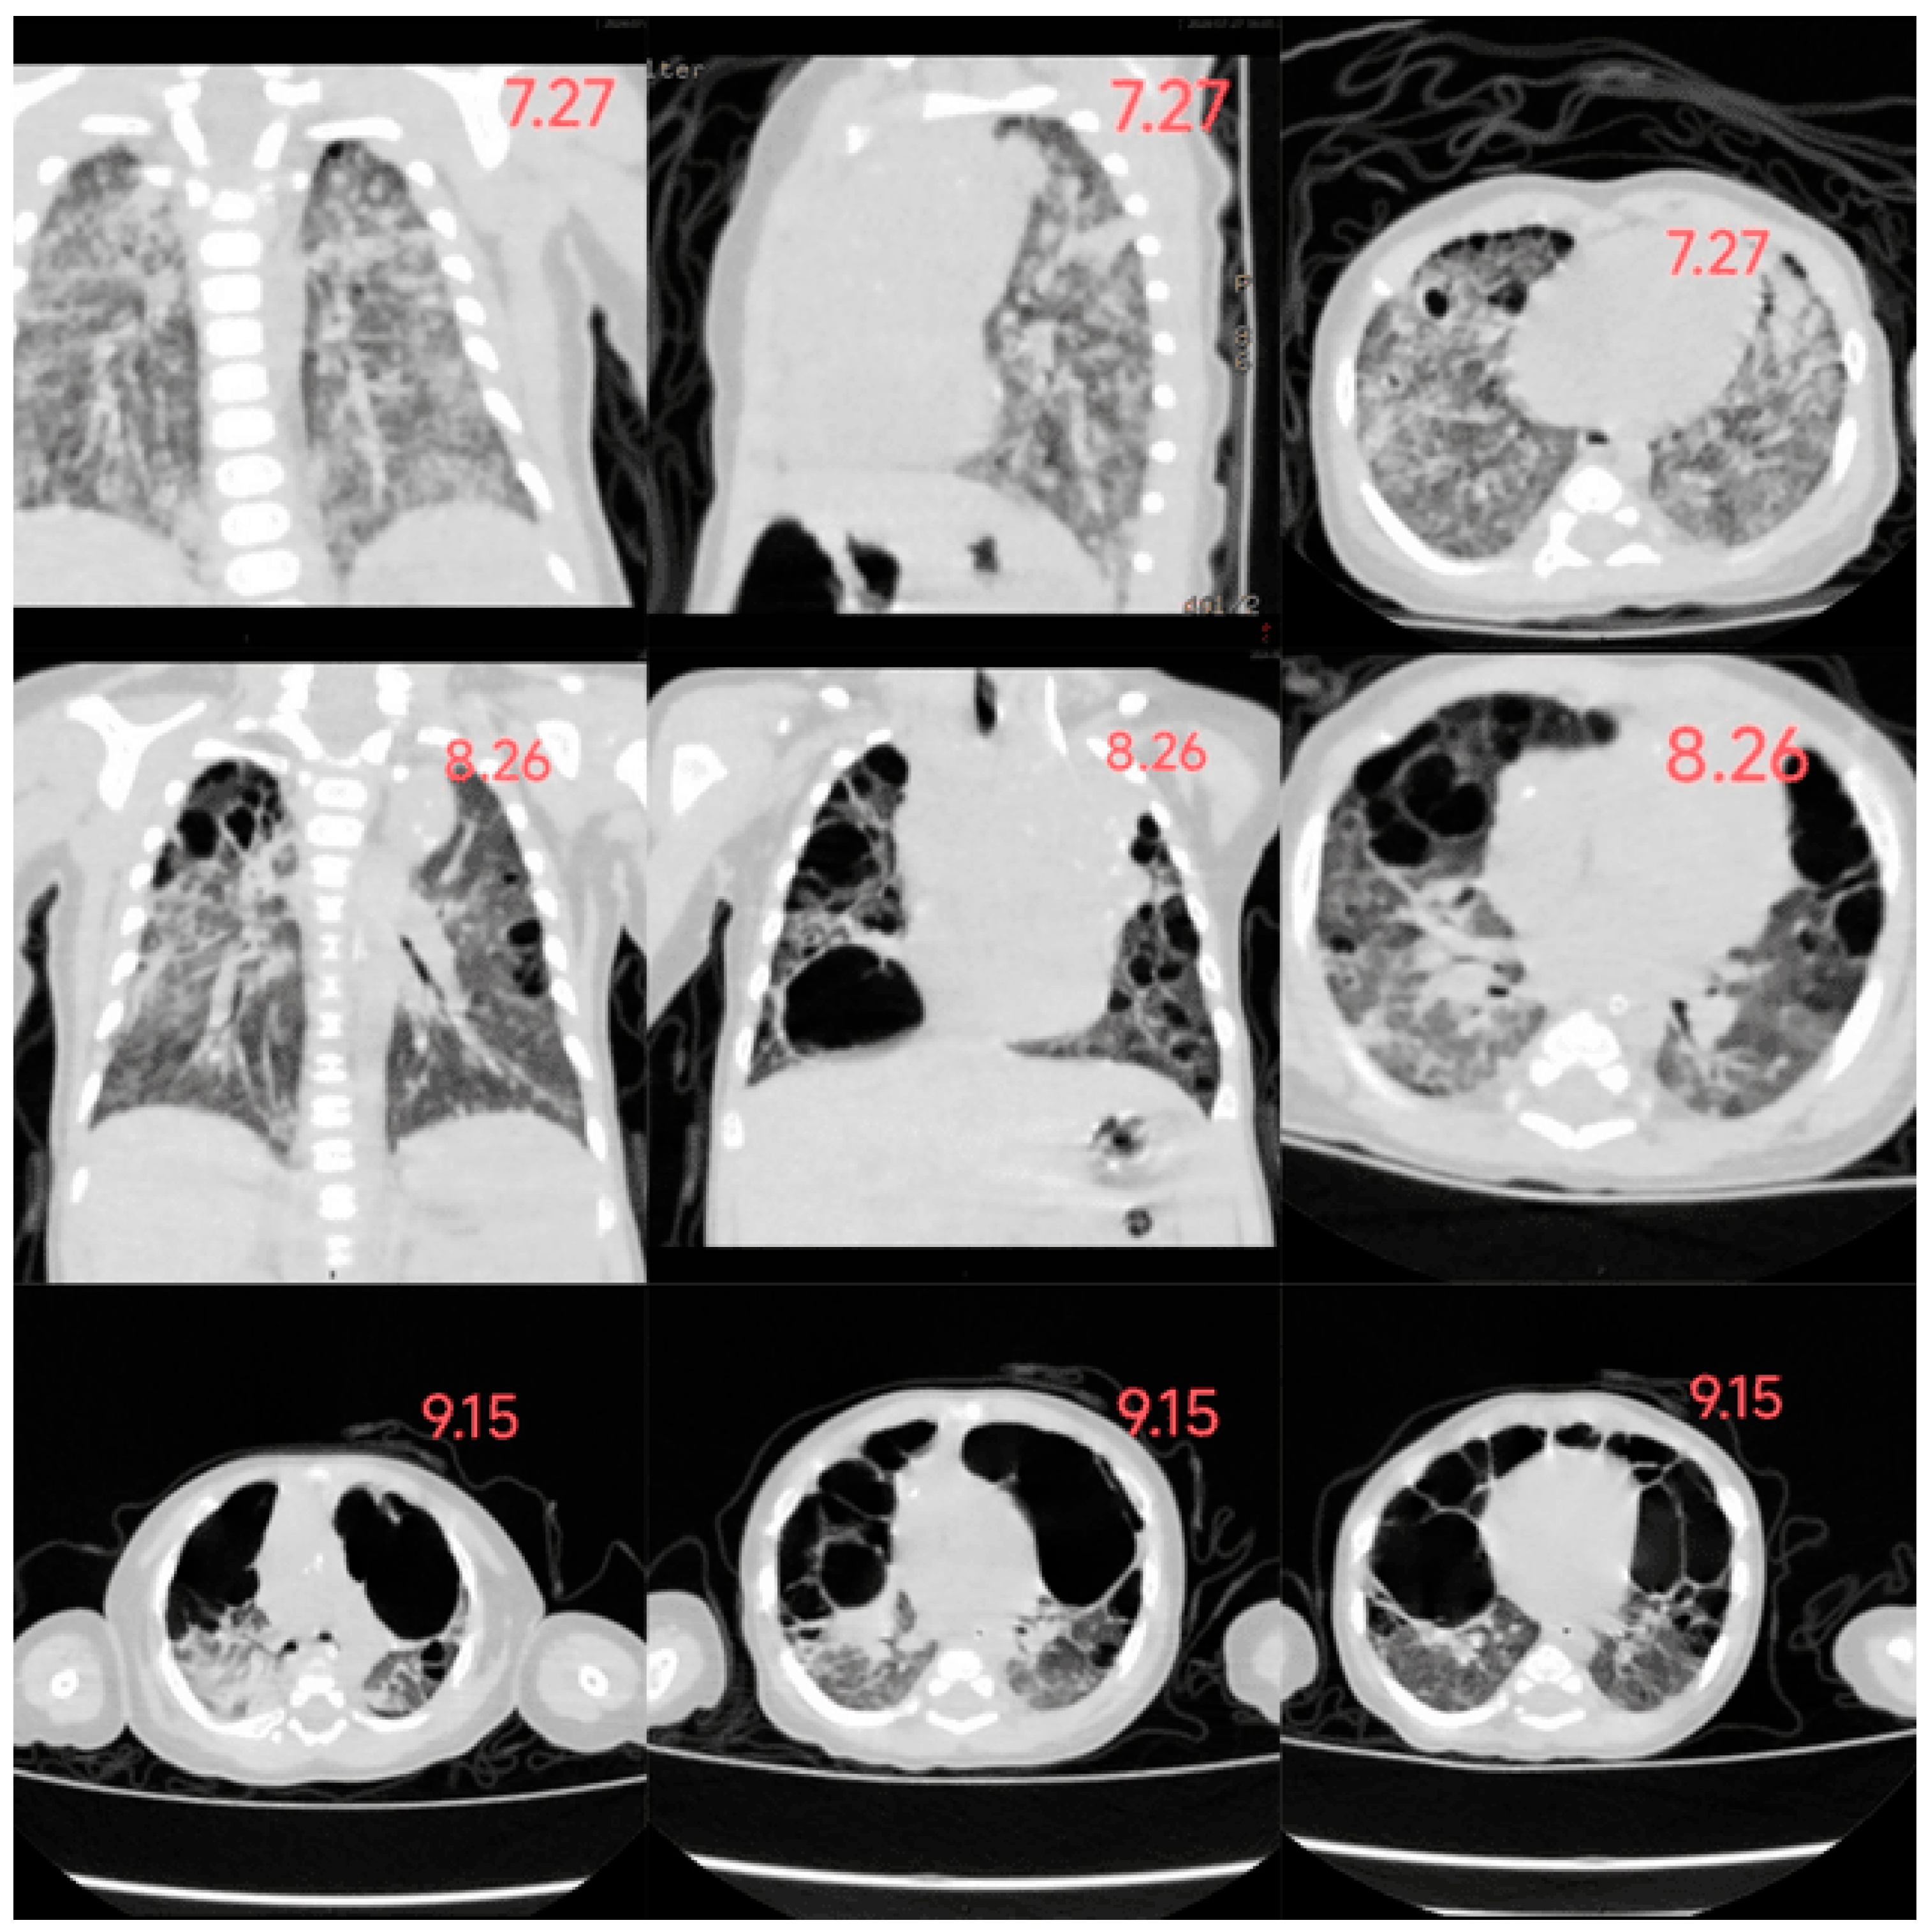

In this case, the infant developed a rash 20 days after birth, gradually spreading across the entire body. The rash presented as scattered millet-sized, round, flat, raised papules and maculopapular lesions, appearing light yellow, yellowish-brown, or dark brown. Some lesions had central crusting with thin scaling on the surface, accompanied by desquamation. However, a timely diagnosis was not made. By the age of 2 months (2 weeks after admission), the rash had worsened and involved the lungs and liver, leading to the development of pulmonary bullae and hepatomegaly. Based on pathological and immunohistochemical findings, the infant was diagnosed with Letterer-Siwe disease. After one month of guideline-directed treatment, follow-up chest imaging revealed further progression of pulmonary bullae, along with pancreatic involvement. Ultimately, the infant passed away, and the overall condition exhibited a progressively worsening trend. (Figure 3: The changes in the infant's chest CT)

Figure 3. The changes in the infant's chest CT.